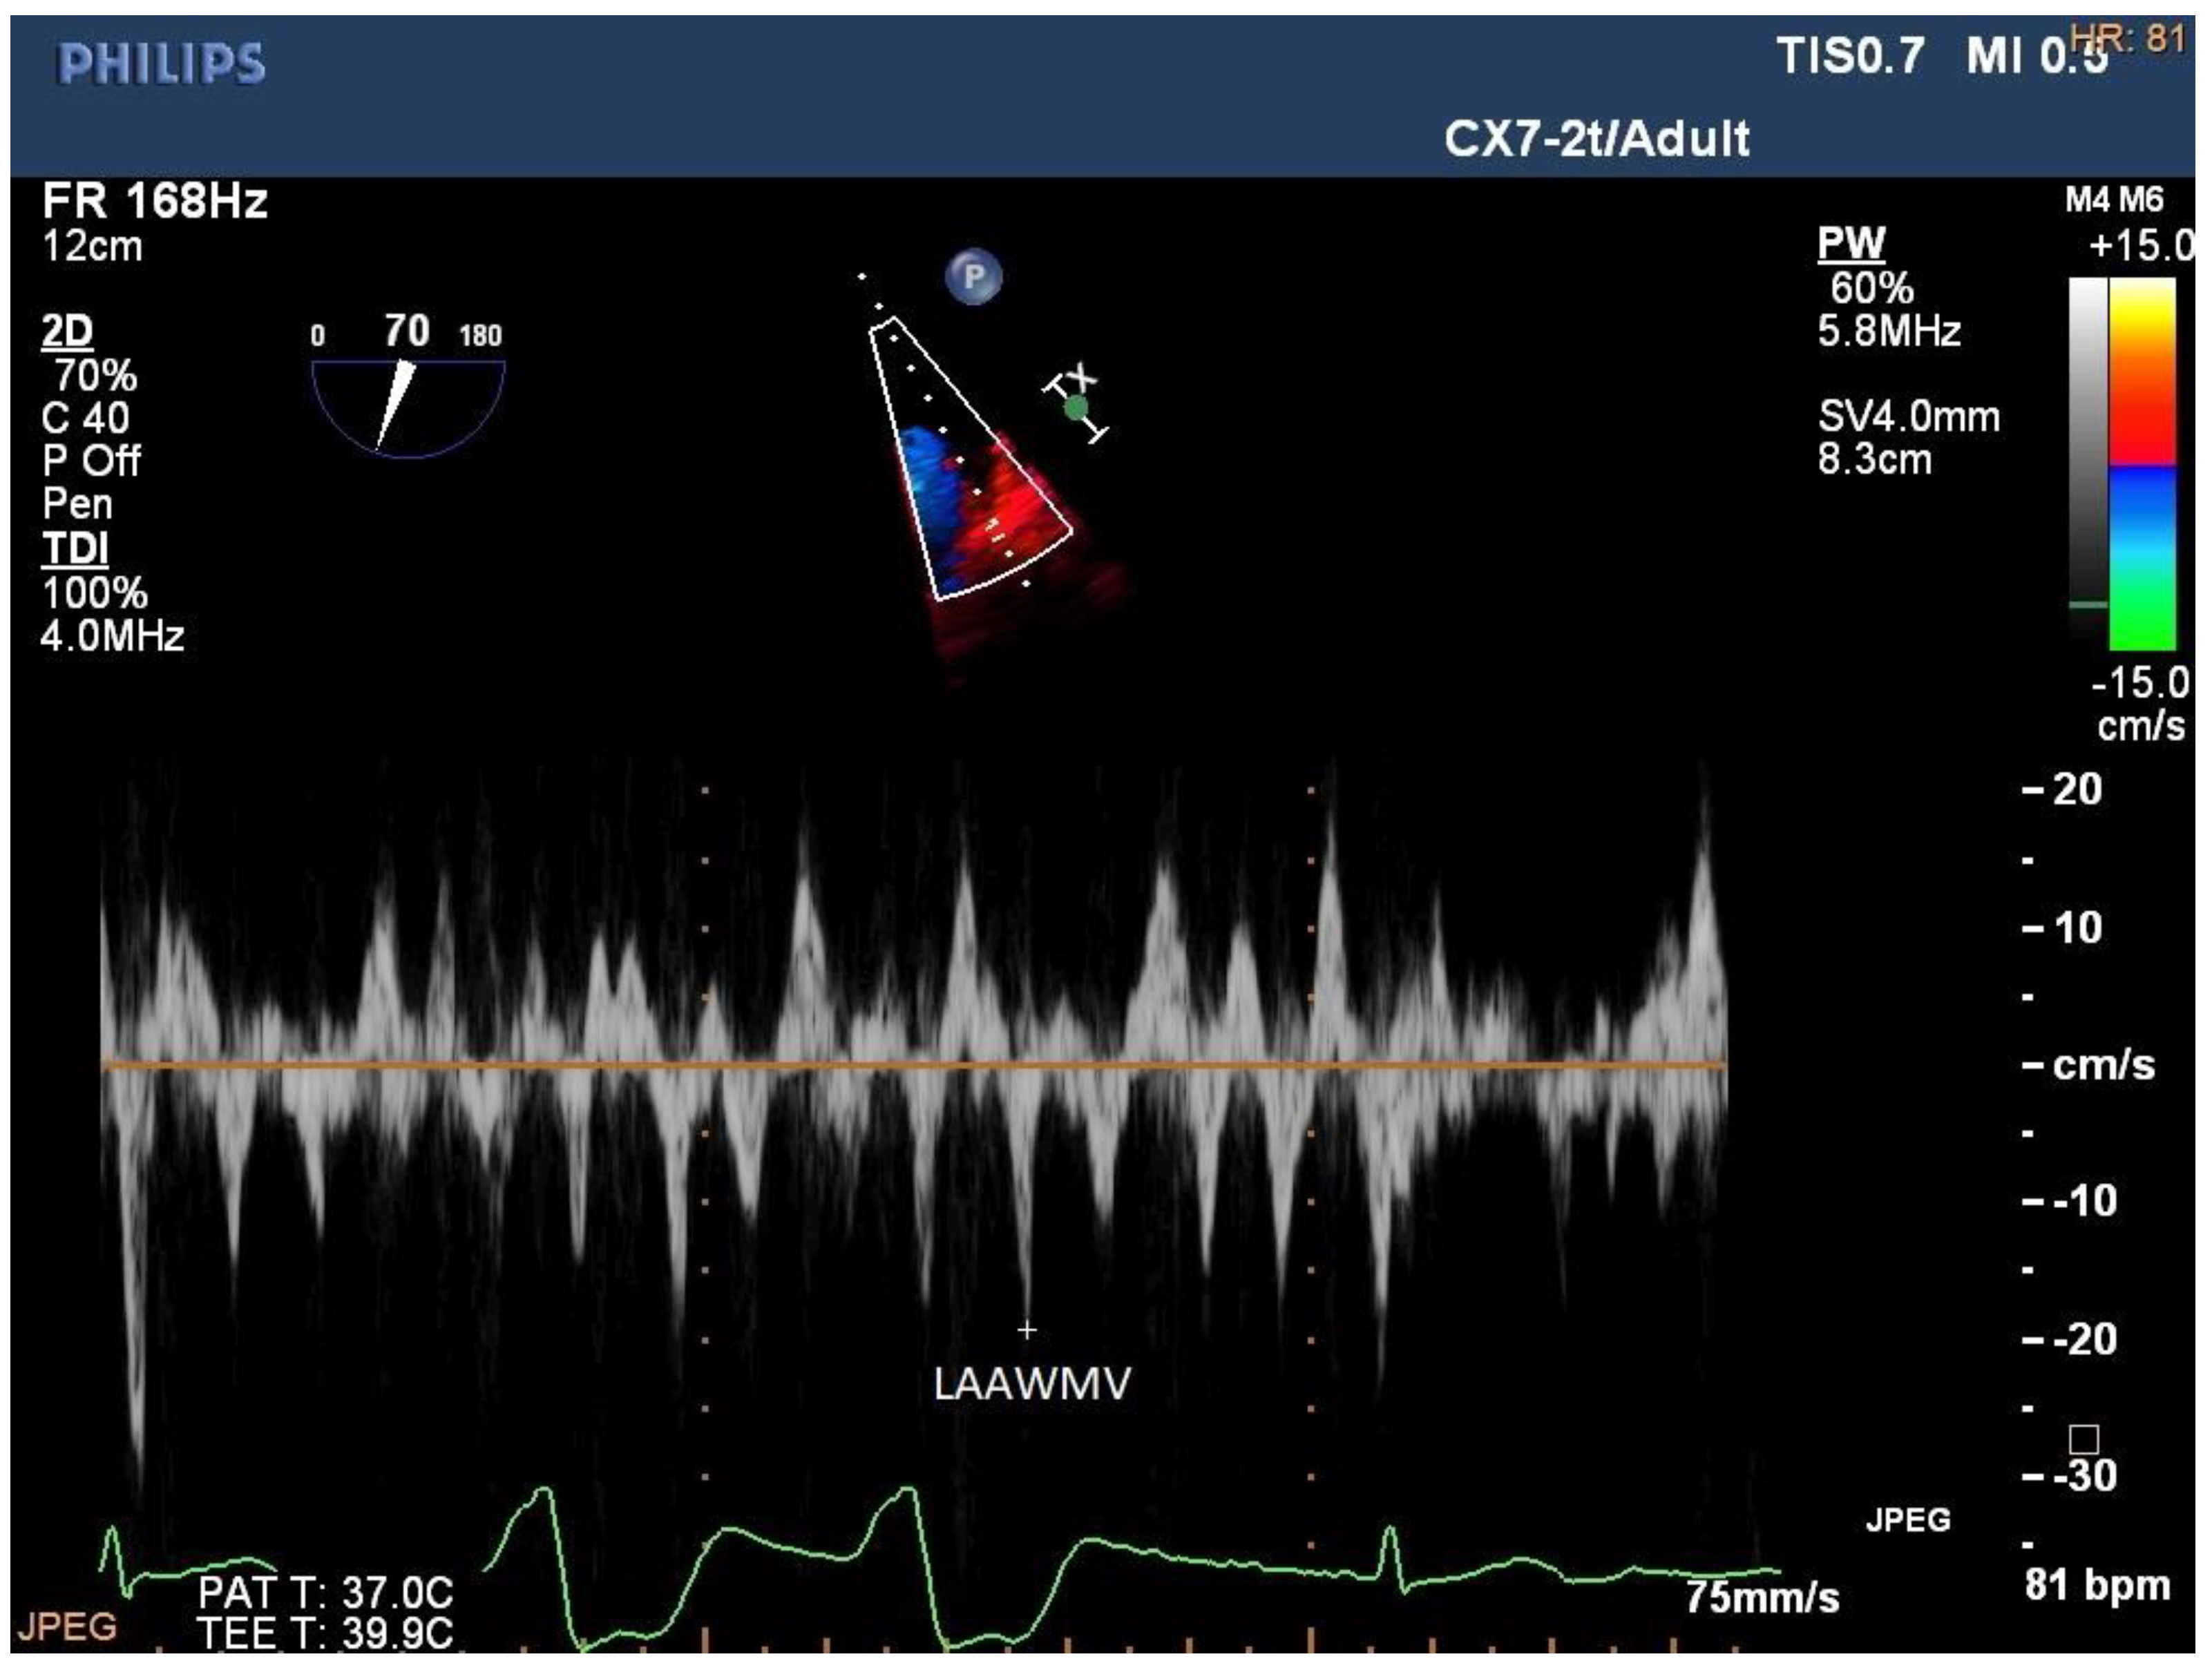

4.2. Left and Right Atrial Emptying Fraction

Figure 1. Left atrial fibrillatory contraction flow (Afc). Pulsed-wave Doppler of mitral filling in the apical four-chamber projection during atrial fibrillation. Velocity time integral (VTI) and AFc velocity measurement. AFc VTI 3.8 cm. AFc V 21 cm/s.